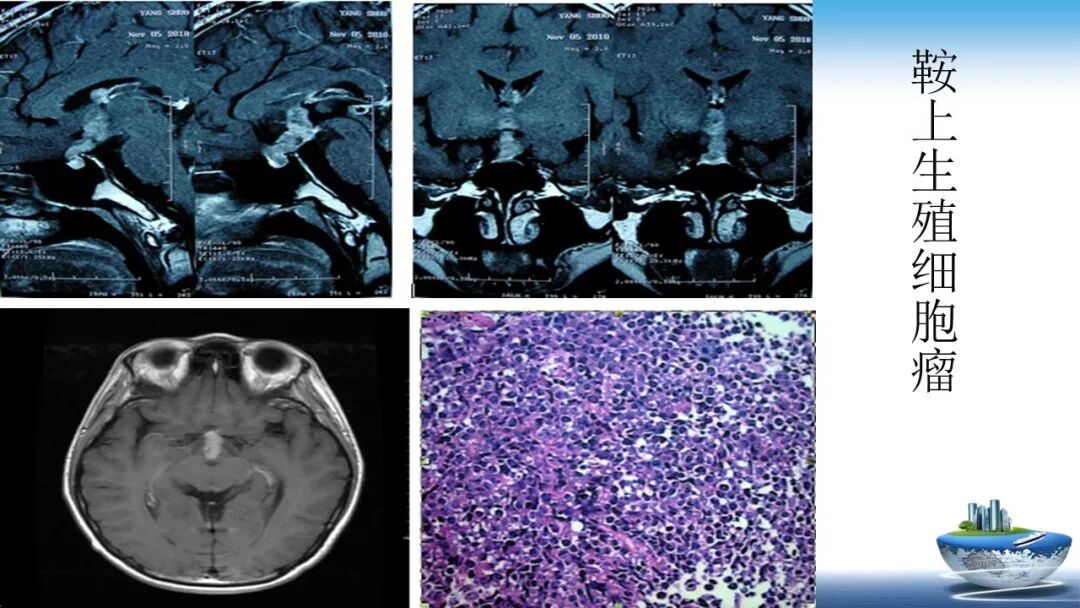

立体定向活检在脑干中线病变精准诊断中的作用

今天为大家带来的是中国人民解放军总医院第六医学中心(原中国人民解放军海军总医院)王亚明、于新、张剑宁带来的精彩课题分享:立体定向活检在脑干中线病变精准诊断中的作用,欢迎观看、阅读!